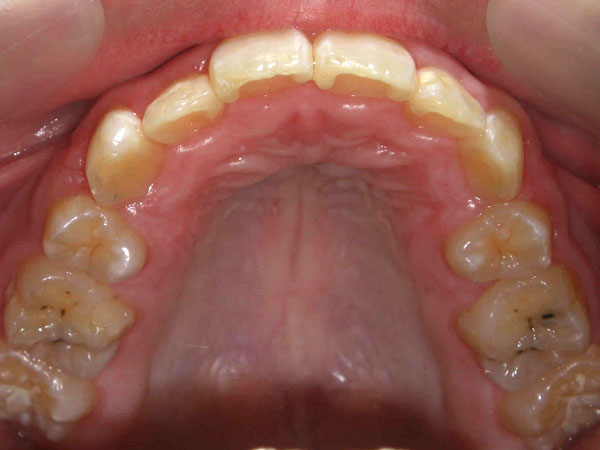

歯が重なり合って、でこぼこした歯並びの状態のことをそう生と言います。歯と顎の大きさの調和がとれないために起きる症状です。